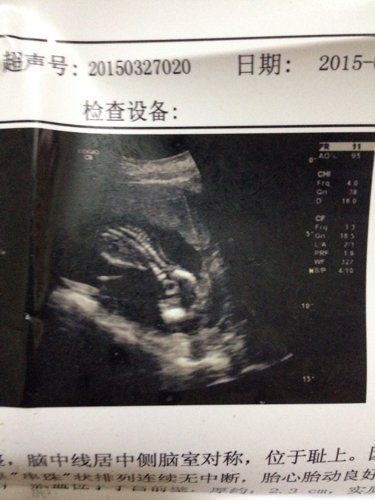

求有经验的好心人帮忙看看是男孩还是女孩

这个能看不出来的,和经验无关。 17周的时候医生能看出来一点但是不确定,等到20周的时候应该就能确定的辨别了,不过医院是 不会告诉你的,你的b超上也不会把性别部位给你显示的,彩超能够清晰的看出来。不过看你怎么问问题了。有些医院会暗示:刚才还不让看。或者你做b超的时候随意的所,哎也不知道该准备男宝宝的...衣服还是女宝宝的衣服。